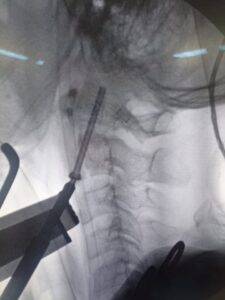

نجح فريق جراحة المخ والأعصاب بالمستشفى في إجراء عملية نادرة ومعقدة أنقذت شابًا كان يعاني من ألم شديد بالرقبة وفقدان القدرة على الحركة، نتيجة كسر بالفقرات العنقية، مع كسر بالناتئ الفقري للفقرة العنقية الثانية، مما تسبب في ضغط على الحبل الشوكي.

وقد تم التدخل الجراحي العاجل لتثبيت الكسر من خلال فصل عضلات البلعوم والمريء والقصبة الهوائية بجوار الشريان السباتي، وهي من أكثر جراحات العمود الفقري تعقيدًا وحساسية.